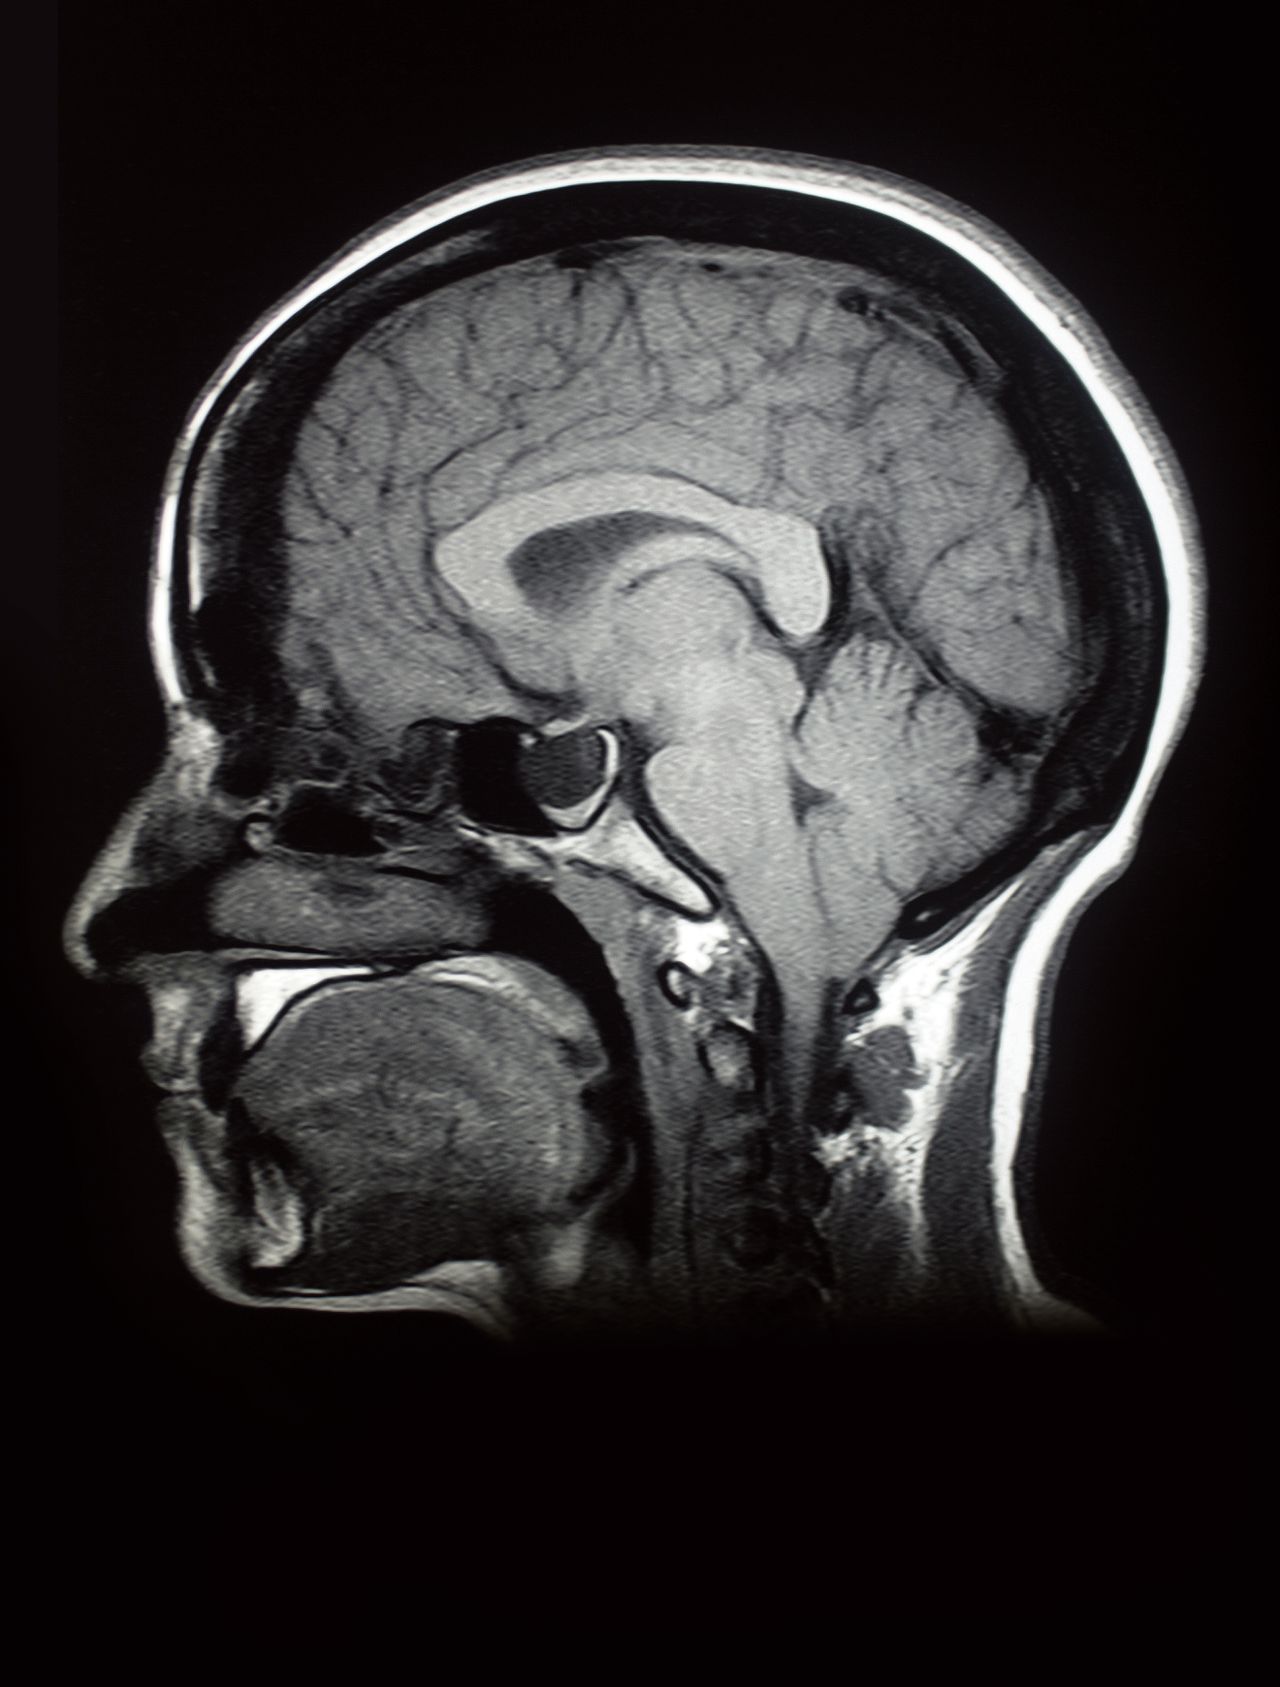

Фото Голов Мозга

Фото Голов Мозга 141 фотографий